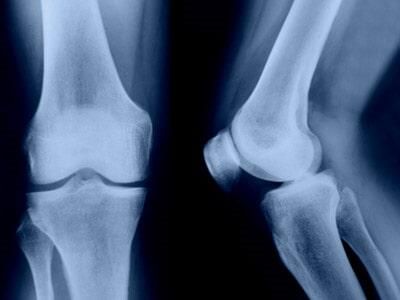

• Rodilla

La Ortopedia es la especialidad médica que se dedica al tratamiento del sistema musculoesquelético: huesos, articulaciones, ligamentos, músculos y tendones.

Traumatología se especializa en el tratamiento de lesiones traumáticas, congénitas o adquiridas en huesos, músculos, articulaciones y tendones, algunos de estas lesiones pueden requerir cirugía.